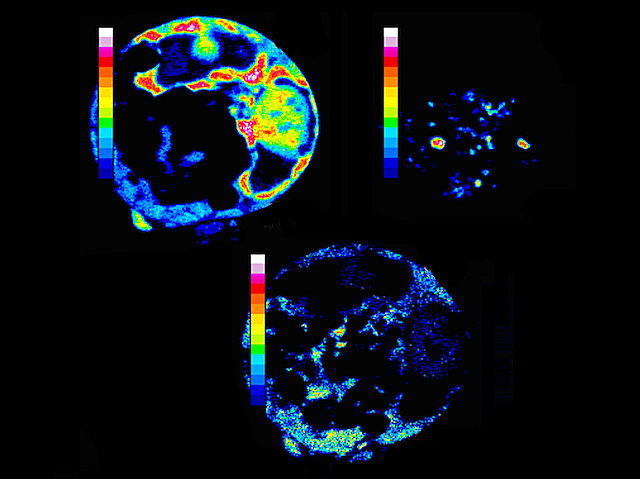

Cisplatin – a chemotherapy drug based on the metal platinum – has been used to treat cancers for many years; however, resistance to platinum has become an issue, prompting researchers to look for other metal compounds. Researchers tracked the activity of different compounds based on the metals zinc (top left), osmium (top right) and calcium (bottom) in ovarian cancer cells using x-ray fluorescence. Colours shown represent the compound’s concentration – white being strongest. The team could see that one, called organo-osmium FY26, made its way into and was concentrated in the cell’s energy-producing mitochondria (highlighted in red top right), killing the cell from the inside. Organo-osmium FY26 is fifty times more active and also more selective than cisplatin, making it a promising candidate for a new cancer treatment.